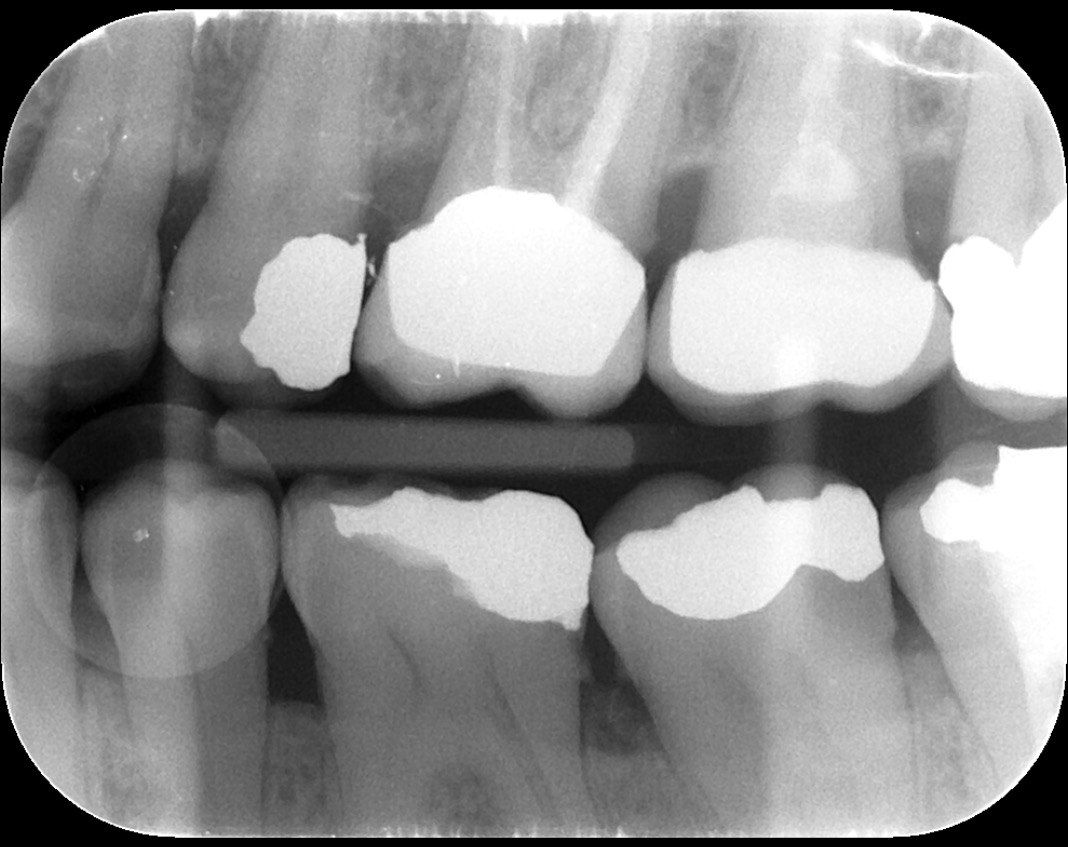

Question 1: What is the condition of the mesial surface of the tooth # 2.6?

Question 2. What is the condition of the mesial of the tooth # 2.7?

Question 3. What is the condition of the distal surface of the tooth # 2.7 and mesial surface of the tooth # 2.8 respectively?